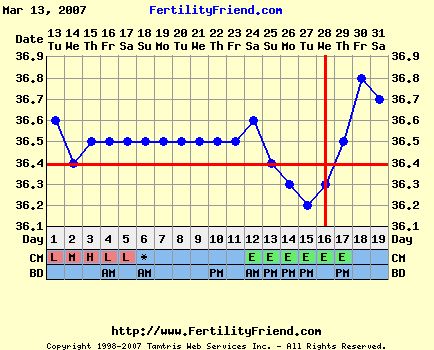

annyira átérzem a helyzeted! De a hőd középidőben mászott lefelé, és most elkezdett fölfelé... Ez jóóóóóó!!! És ti megtettetek mindent, úgyhogy tényleg nyugi. A párod meg egy tünemény! Szerintem ha megkérnéd, hogy maradjon otthon veled és tartsa a lábadat egész nap gyertyában, azt is megtenné!